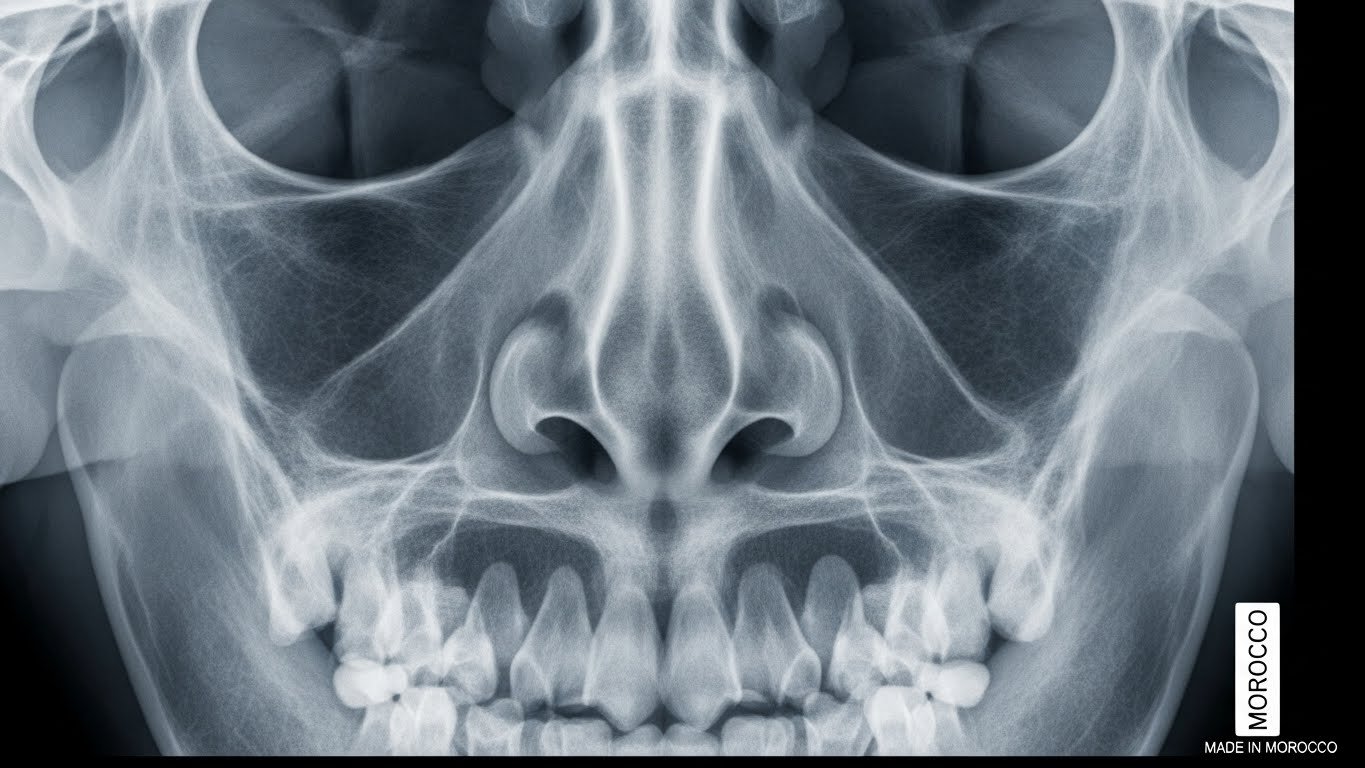

Une radiographie des os propres du nez est un examen d’imagerie médicale qui utilise les rayons X pour obtenir des images détaillées de la structure osseuse de votre nez. Contrairement à ce que son nom peut laisser penser, cet examen n’est ni compliqué ni invasif.

Les « os propres du nez » sont les deux petits os qui forment la partie supérieure de votre nez, juste en dessous du front. Ils constituent ce que les médecins appellent la « pyramide nasale ». Ces os sont particulièrement fragiles et vulnérables aux chocs, ce qui explique pourquoi ils se fracturent facilement lors d’un traumatisme facial.